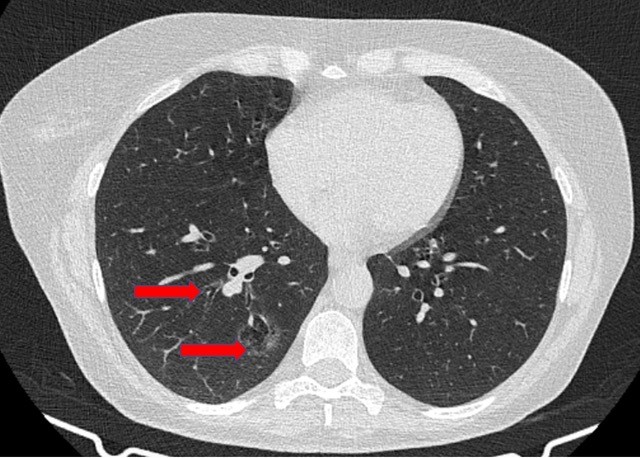

Anatomic sublobar resections have been used primarily for benign pulmonary lesions, lung metastases, and early stage lung cancer. There are many recent studies that support the oncological results of anatomic sublobar resections compared to lobectomy in terms of recurrence and overall survival [1-8]. In addition, the procedure’s performance through minimally invasive procedures is possible by experienced teams [9, 10]. The authors present a sublobar resection performed for a 50-year-old woman who was diagnosed with a 2.5 cm diffuse ground glass opacity adenocarcinoma in the right basal segments (Figure 1) that was identified during chronic asthma follow-up.

Figure 1. Preoperative computed tomography scan